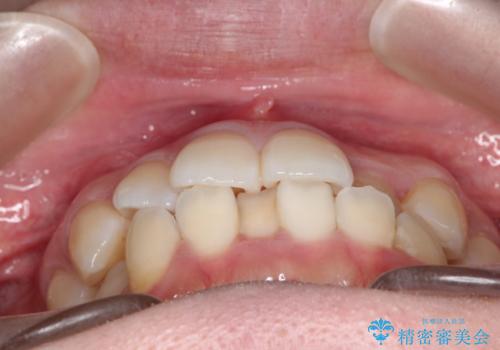

【ワイヤー矯正】口元を下げたい、下の歯の凹凸を無くしたい

- 主訴:口元を下げて前突感を無くしたい、下の歯の凹凸も無くしたい

右側第二小臼歯、左側第一小臼歯、下顎両側第一大臼歯を抜歯しワイヤ-矯正を行いました。

骨格的顎の変位を認めたため、顔貌に対しピッタリ上下の歯の正中を合わせることは難しいと説明し、上下左右計4本小臼歯を抜歯しワイヤー矯正治療を行いました。